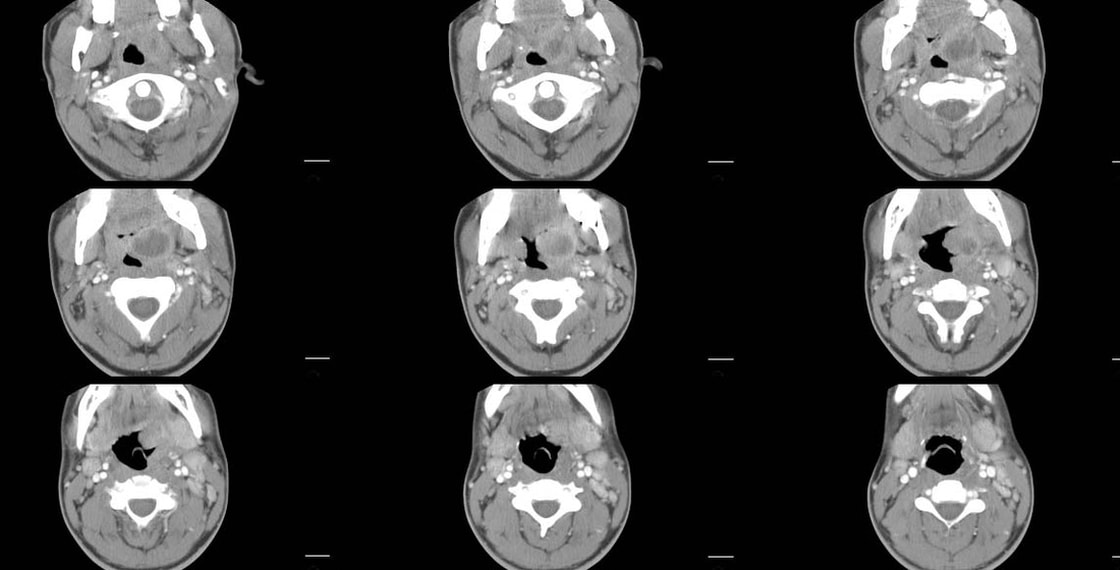

17 year old male. ​

Axial head CT with contrast

1.  What are the primary findings?

2.  List your differential diagnosis.

3.  What is the appropriate treatment?